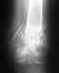

Еще раз рентгеновские снимки.

Кликните для загрузки файла Rentgen.JPG

70KB (71828 bytes)